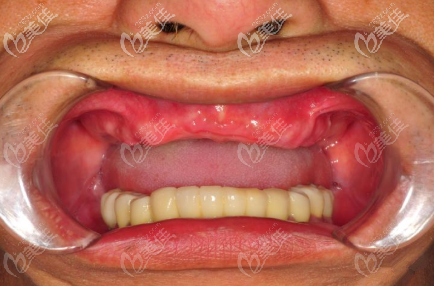

術(shù)后照片:

即刻修復(fù)種植后,手術(shù)當(dāng)天戴牙。種植體品牌選的是諾貝爾Active,也是諾貝爾nobel種植體三大型號里面比較常用的。這個案例中諾貝爾Active種植體的價格為2W一顆,收費標(biāo)準(zhǔn)在西安來說適中。